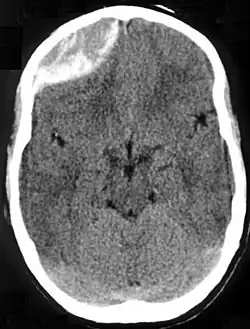

Nontraumatic epidural hematoma in a young woman. The grey area in the top right is organizing hematoma, causing midline shift and compression of the ventricle. -